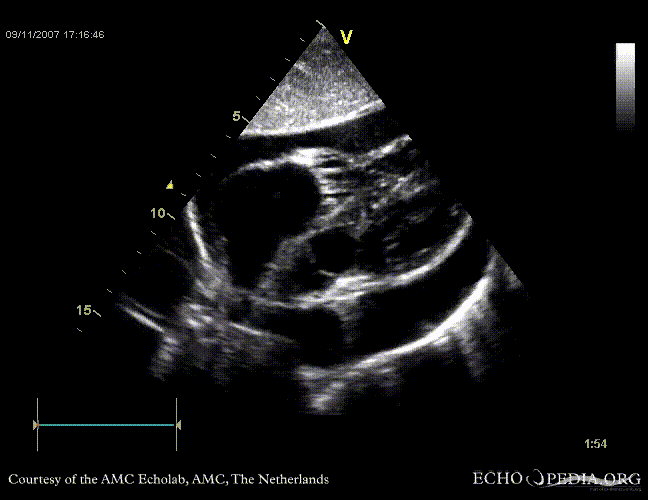

Tamponade

Courtesy of:

J. Vleugels, AMC, The Netherlands

tamponade 3